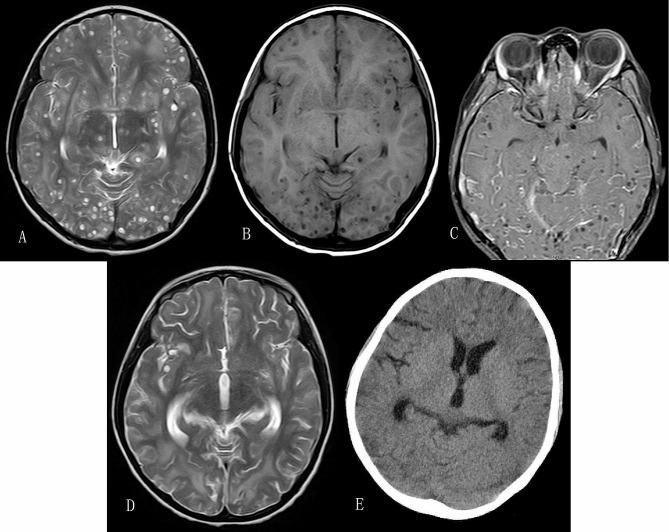

Here we present a case of ten-year-old Tibetan girl who developed headache and vomiting. Her brain magnetic resonance imaging (MRI) illustrated lots of intracranial cystic lesions, and no obvious extracranial lesions were found. Serum immunoglobulin G antibodies against cysticerci were positive by the use of an enzyme-linked immunosorbent assay (ELISA). These results in combination with her medical history were in line with massive neurocysticercosis. The patients recovered well after supportive management and antiparasitic treatment.

本案例介绍了一位十岁的藏族女孩,她出现头痛和呕吐。她的脑部磁共振成像(MRI)显示颅内有许多囊状病变,没有明显的颅外病变。酶联免疫吸附试验(ELISA)显示血清免疫球蛋白 G 抗体对囊虫呈阳性。这些结果结合她的病史,符合巨囊型脑囊虫病。患者在支持性治疗和驱虫治疗后恢复良好。